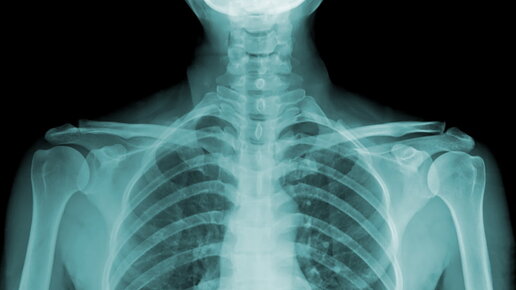

Что характеризует легкие курильщика? Легкие курильщика черные и покрыты густым, липким налетом. Сигаретный дым содержит более 4 000 тысяч химических веществ, вредных для здоровья, включая многочисленные канцерогены. Дыхательные пути темнеют после выкуривания всего одной пачки сигарет. Именно воздействие смол, горячих газов и многочисленных токсичных соединений ответственно за нарушение активности альвеолярных макрофагов - естественных "ресничек", очищающих легкие. Цилиарный механизм у некурящего человека эффективно удаляет все токсины из дыхательных путей...